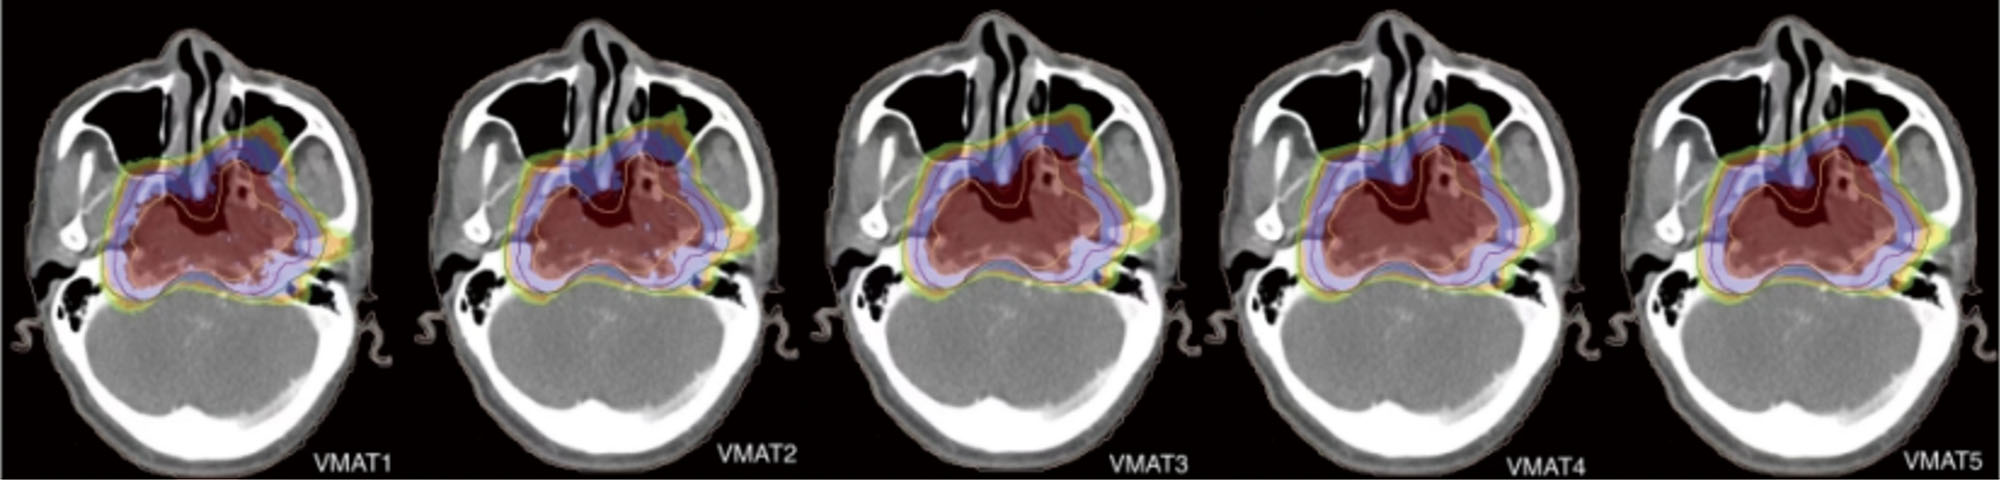

目的 分析Monaco系统不同剂量计算网格尺寸对T4期鼻咽癌靶区及靶区周围重要危及器官(OAR)的物理和生物剂量学的影响。方法 选取2020年10月至2022年4月在云南省肿瘤医院放疗科进行放疗的18例T4期鼻咽癌患者,在Monaco 5.11.03系统中完成靶区和OAR的勾画,以靶区优先的优化模式在3 mm网格制定容积弧形调强放疗(VMAT)计划;复制3 mm网格组计划,不改变其他的任何参数,分别在1、2、4和5 mm网格重新制定物理计划,再将5个计划归一到处方剂量包绕95%的靶区体积。比较各网格组靶区的计划时间、D2%、D50%、D98%、适形度指数(CI)、均匀性指数(HI)、靶区梯度指数(GI)、计算靶区的肿瘤控制率(TCP)以及靶区周围重要OAR的D2%、Dmean值。结果 计划大体肿瘤靶区(PGTVp):1、2、3、4、5 mm组的D2%分别为(76.94±0.66)、(75.98±0.76)、(75.56±0.67)、(75.67±0.73)、(75.94±0.85)Gy,差异有统计学意义(F=9.86,P<0.001);1、2、3、4、5 mm组的CI分别为0.75±0.05、0.78±0.04、0.78±0.05、0.79±0.04、0.78±0.04,差异有统计学意义(F=2.61,P=0.041);各分组间D50%、D98%、HI、等效均匀剂量(EUD)和肿瘤控制率(TCP)的差异均有统计学意义(H=17.14,P=0.002;F=9.35,P<0.001;H=25.43,P<0.001;F=5.85,P<0.001;H=17.65,P=0.001),各分组间GI差异无统计学意义(P>0.05)。两两比较发现,2、3、4、5 mm组D2%与1 mm组相比,5 mm组D50%与2、3 mm组相比,4 mm组D98%与1、2 mm组相比,5 mm组D98%与1、2、3 mm组相比,5 mm组CI与1 mm组相比,2、3、4、5 mm组HI与1 mm组相比,3 mm组EUD与1 mm组相比,5 mm组EUD与2、3 mm组相比,3 mm组TCP与1 mm组相比,5 mm组TCP与3 mm组相比,差异均有统计学意义(均P<0.05)。计划大体肿瘤淋巴结靶区(PGTVn):1、2、3、4、5 mm组的D2%分别为(76.36±0.59)、(75.36±0.62)、(75.04±0.68)、(75.25±0.72)、(75.39±0.77)Gy,差异有统计学意义(F=10.32,P<0.001);1、2、3、4、5 mm组的HI分别为1.08(1.08,1.08)、1.07(1.06,1.07)、1.06(1.06,1.07)、1.06(1.06,1.07)、1.06(1.06,1.08),差异有统计学意义(H=22.00,P<0.001);各分组间D50%、D98%和EUD的差异均有统计学意义(H=11.79,P=0.019;H=20.49,P<0.001;F=12.14,P=0.016);各分组间CI、GI差异均无统计学意义(均P>0.05)。两两比较发现,2、3、4、5 mm组D2%与1 mm组相比,4 mm组D98%与1 mm组相比,5 mm组D98%与1、2 mm组相比,2、3、4 mm组HI与1 mm组相比,3 mm组EUD与1 mm组相比,差异均有统计学意义(均P<0.05)。计划原发肿瘤临床靶区1(PCTVp1):1、2、3、4、5mm组的D2%分别为(76.59±0.63)、(75.64±0.65)、(75.64±0.98)、(75.41±0.70)、(75.71±0.84)Gy,差异有统计学意义(F=9.53,P<0.001);1、2、3、4、5 mm组的D50%分别为(72.09±0.34)、(71.85±0.39)、(71.82±0.45)、(72.04±0.56)、(72.43±0.66)Gy,差异有统计学意义(F=4.20,P=0.019);其余各指标组间差异均无统计学意义(均P>0.05)。两两比较发现,2、3、4、5 mm组D2%与1 mm组相比,5 mm组D50%与2、3 mm组相比,差异均有统计学意义(均P<0.05)。计划淋巴结临床靶区1(PCTVn1):各指标组间差异均无统计学意义(均P>0.05)。计划临床靶区2(PCTV2):1、2、3、4、5 mm组的D2%分别为(75.57±0.50)、(74.87±0.67)、(74.51±0.51)、(74.61±0.63)、(75.00±0.74)Gy,差异有统计学意义(F=8.27,P<0.001);其余指标各组间差异均无统计学意义(均P>0.05)。两两比较发现,2、3、4 mm组D2%与1 mm组相比,差异均有统计学意义(均P<0.05)。1、2、4、5 mm组物理计划计算时间分别为987.00(848.00,1 091.00)、120.50(99.75,134.00)、26.00(24.00,34.25)、21.50(18.75,34.75)s,差异有统计学意义(H=61.62,P<0.001),两两比较发现,4 mm组与1、2 mm组,5 mm组与1、2 mm组的计划计算时间相比,差异均有统计学意义(均P<0.05)。靶区周围OAR的剂量学参数各指标组间差异均无统计学意义(均P>0.05)。结论 T4期鼻咽癌在制定放疗物理计划时,靶区及靶区周围重要OAR的物理剂量和生物剂量随剂量计算网格尺寸的改变而改变。综合考虑物理计划质量及计算时间,在Monaco系统制定T4期鼻咽癌患者的VMAT计划时,可先在3 mm计算网格进行计划优化,并将计划复制到1 mm计算网格重新计算。

Objective To analyze the effects of different dose calculation grid size of Monaco system on the physical and biological dosimetry of target area and organ at risk (OAR) in T4 nasopharyngeal carcinoma. Methods A total of 18 patients with stage T4 nasopharyngeal carcinoma who received radiotherapy in the Department of Radiotherapy of Yunnan Cancer Hospital from October 2020 to April 2022 were selected to complete the delineation of target areas and OAR in the Monaco 5.11.03 system,and the volumetric intensity modulated arc therapy (VMAT) plan was developed on the 3 mm grid with the optimization mode of target area priority. The 3 mm grid group plan was replicated without changing any other parameters,and the physical plan was re-established on the 1,2,4 and 5 mm grids,and then the five plans were normalized to the prescription dose to cover 95% of the target volume. The planning time,D2%,D50%,D98%,conformity index (CI),homogeneity index (HI),gradient index (GI),tumor control probability (TCP),D2% and Dmean of important OAR around the target area were calculated and statistically analyzed. Results Planning primary tumor gross target volume(PGTVp):The D2% of 1,2,3,4 and 5 mm groups were (76.94±0.66),(75.98±0.76),(75.56±0.67),(75.67±0.73) and (75.94±0.85) Gy,respectively,with a statistically significant difference (F=9.86,P<0.001). The CI of 1,2,3,4 and 5 mm groups were 0.75±0.05,0.78±0.04,0.78±0.05,0.79±0.04 and 0.78±0.04,respectively,with a statistically significant difference (F=2.61,P=0.041). There were statistically significant differences in D50%,D98%,HI,equivalent uniform dose (EUD) and tumor control probability (TCP) among the groups (H=17.14,P=0.002; F=9.35,P<0.001; H=25.43,P<0.001 ; F=5.85,P<0.001; H=17.65,P=0.001). There was no statistically significant difference in GI among the groups (P>0.05). Pairwise comparison showed that D2% in 2,3,4,5 mm groups compared with 1 mm group,D50% in 5 mm group compared with 2,3 mm groups,D98% in 4 mm group compared with 1,2 mm groups,D98% in 5 mm group compared with 1,2,3 mm groups,CI in 5 mm group compared with 1 mm group,HI in 2,3,4,5 mm groups compared with 1 mm group,EUD in 3 mm group was compared with 1 mm group,EUD in 5 mm group compared with 2,3 mm groups,TCP in 3 mm group compared with 1 mm group,and TCP in 5 mm group compared with 3 mm group,there were statistically significant differences (all P<0.05). Planning nodal gross target volume (PGTVn):The D2% of 1,2,3,4 and 5 mm groups were (76.36±0.59),(75.36±0.62),(75.04±0.68),(75.25±0.72) and (75.39±0.77) Gy,respectively,with a statistically significant difference (F=10.32,P<0.001). The HI of 1,2,3,4 and 5 mm groups were 1.08(1.08,1.08),1.07(1.06,1.07),1.06(1.06,1.07),1.06(1.06,1.07),1.06(1.06,1.07),1.06(1.06,1.08),respectively,with a statistically significant difference (H=22.00,P<0.001);There were statistically significant differences in D50%,D98% and EUD among the groups (H=11.79,P=0.019; H=20.49,P<0.001; F=12.14,P=0.016). Pairwise comparison showed that there were statistically significant differences in D2% between 2,3,4,5 mm groups and 1 mm group,D98% between 4 mm group and 1 mm group,D98% between 5 mm group and 1,2 mm groups,HI between 2,3,4 mm groups and 1 mm group,and EUD between 3 mm group and 1 mm group (all P<0.05). Planning primary tumor clinical target volume 1 (PCTVp1): The D2% of 1,2,3,4 and 5 mm groups were (76.59±0.63),(75.64±0.65),(75.64±0.98),(75.41±0.70) and (75.71±0.84) Gy,respectively,with a statistically significant difference (F=9.53,P<0.001). The D50% of 1,2,3,4,5 mm groups were (72.09±0.34),(71.85±0.39),(71.82±0.45),(72.04±0.56),(72.43±0.66) Gy,respectively,with a statistically significant difference (F=4.20,P=0.019). There was no statistically significant difference in the other indexes among the groups (all P>0.05). Pairwise comparison showed that there were statistically significant differences in D2% between 2,3,4,5 mm groups and 1 mm group,and in D50% between 2,3 mm groups and 1 mm group (all P<0.05). Planning nodal clinical target volume 1(PCTVn1): There were no statistically significant differences in all indexes among the groups (all P>0.05). Planning clinical target volume 2 (PCTV2): The D2% of 1,2,3,4 and 5 mm groups were (75.57±0.50),(74.87±0.67),(74.51±0.51),(74.61±0.63) and (75.00±0.74) Gy,respectively,with a statistically significant difference (F=8.27,P<0.001). Pairwise comparison showed that the D2% of the 2,3,4 mm groups were significantly different from that of the 1 mm group (all P<0.05). The calculation time of physical plan in 1,2,4 and 5 mm groups was 987.00(848.00,1 091.00),120.50(99.75,134.00),26.00 (24.00,34.25) and 21.50(18.75,34.75)s,respectively,with a statistically significant difference (H=61.62,P<0.001). Pairwise comparison showed that there were statistically significant differences in the calculation time between 4 mm group and 1,2 mm groups,5 mm group and 1,2 mm groups (all P<0.05). There was no statistically significant difference in the dosimetric parameters of OAR around the target area among the groups (all P>0.05). Conclusion The physical dose and biological dose of the important OAR around the target area and the target area change with the change of dose calculation grid size when formulating the physical plan of radiotherapy for T4 nasopharyngeal carcinoma. Considering the quality of the physical plan and the calculation time,when the Monaco system formulates the VMAT plan for T4 nasopharyngeal carcinoma patients,the plan can be optimized on the 3 mm computing grid and copied to the 1 mm computing grid for recalculation.